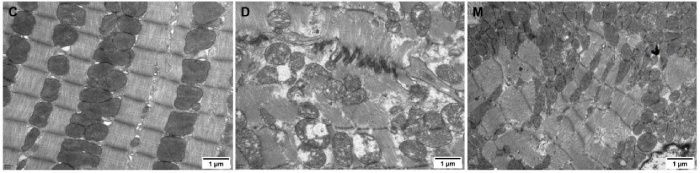

該研究利用透射電鏡測定了MOTS-c對糖尿病心肌超微結(jié)構(gòu)的影響。糖尿病引起心肌纖維排列紊亂和線粒體結(jié)構(gòu)的異常改變,包括心肌細胞排列不規(guī)則、嵴破裂、腫脹和空泡化(圖2)。MOTS-c治療糖尿病大鼠顯著降低心肌線粒體損傷,改善心肌纖維和線粒體結(jié)構(gòu)(圖2)。研究還通過測定檸檬酸合酶的活性,測定了線粒體功能。D組大鼠檸檬酸合酶的活性顯著降低,C組和M組的檸檬酸合酶的活性無統(tǒng)計學差異(圖3g)。

圖2. 各組大鼠心肌組織透射電鏡圖像